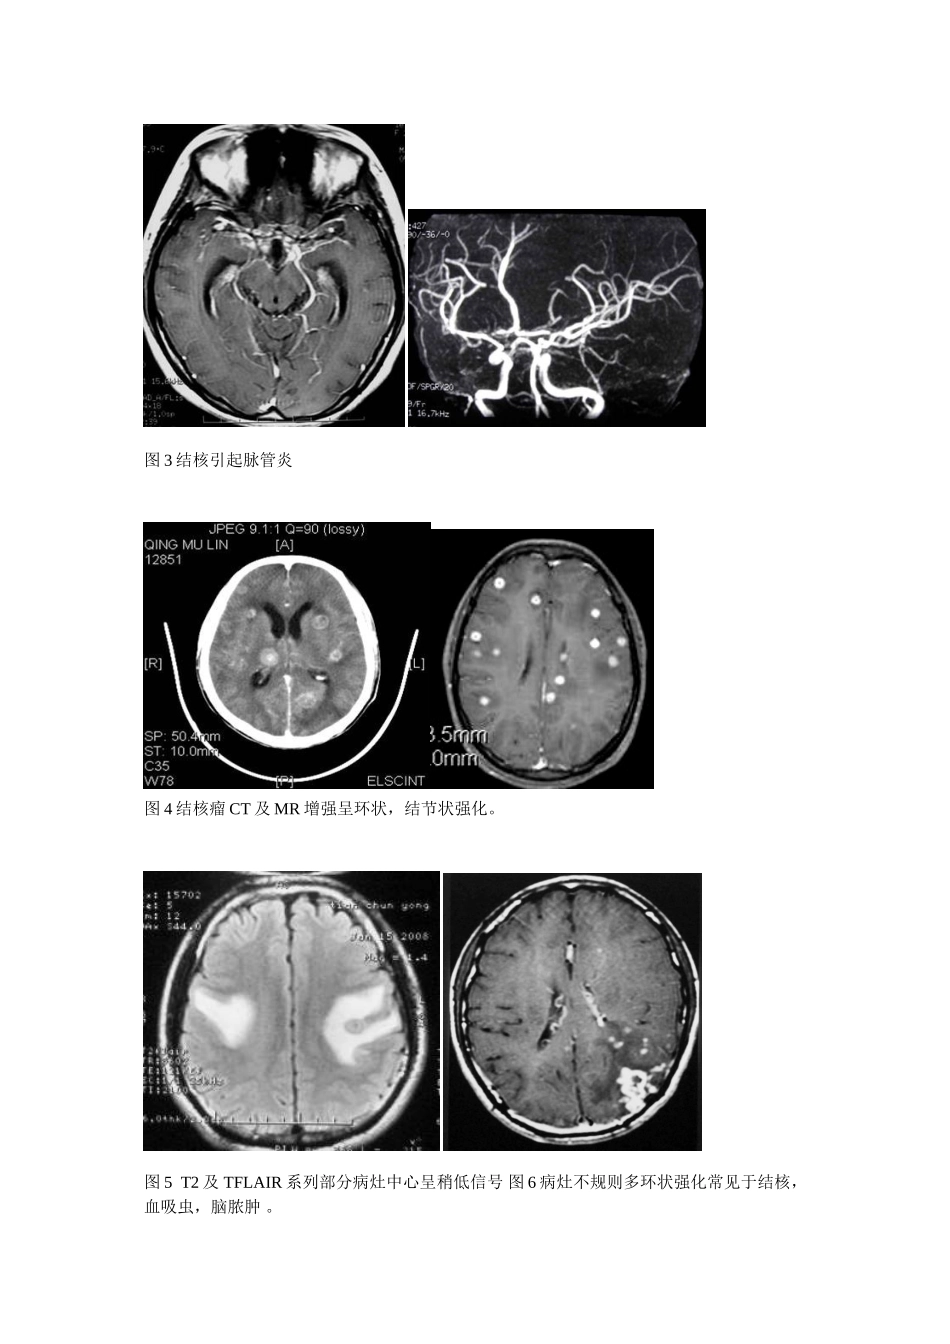

颅内结核CT及MR诊断(附八例报告)郑鹏*杨运红陈凤云戈必喜宜都市中医院443300【摘要】目的:通过对脑及脑膜结核CT及MR影像表现的深刻认识,提高脑及脑膜结核诊断正确率。方法,回顾性分析经临床证实的八例颅内结核CT或MR影像表现,比较影像初诊意见及临床最终诊断结论符合情况,分析其形成原因。并结合相关文献,结果:脑结核影像表现复杂,与多种颅内疾病有相似的影像表现。结论:结脑CT及MR影像表现复杂,与多种颅内疾病有相似的影像表现,必须结合临床及脑积液检查才能作出定性诊断。深刻认识其影像表现,有助于提高脑结核临床诊断正确率,【关键词】颅内结核体层摄影术X线计算机磁共振成像。颅内结核近年发病率有近上升趋势,早期诊断,可明显降低致死致残率,颅内结核一般分两种情况:1结核性脑膜炎及脑膜炎后遗症,2脑结核瘤。由于MR具有高密度分辨率,及对钆剂高度敏感性,头部MRI平扫及增强较CT平扫及增强有明显优势,具有更高病灶检出率。材料和方法本组8例均为临床诊断证实病例,年龄18-37岁,平均25岁,检查方法CT平扫及增强CT直接增强,MR平扫,MR平扫及增强。图1CT平扫基底池闭塞,高密度影充填,左侧丘脑梗塞,幕上积水。图2基底池脑膜增厚强化CT及MR表现。图3结核引起脉管炎图4结核瘤CT及MR增强呈环状,结节状强化。图5T2及TFLAIR系列部分病灶中心呈稍低信号图6病灶不规则多环状强化常见于结核,血吸虫,脑脓肿。图7结核瘤钙化结果:颅内结核影像表现复杂,与多种颅内疾病有相似的影像表现,必须结合临床及脑积液检查才能作出定性诊断。加深对颅内结核CT及MI影像表现的认识,缩小鉴别诊断范围,提示性诊断,有助于提高临床诊断正确率。讨论颅内结核影像表现一般分三种情况:1脑膜炎的表现,2脑结核瘤表现,3继发性表现:如交通性或梗阻性脑积水,脑外积液、脑梗塞、软化、出血及脑萎缩等,1脑膜炎的表现:结核性脑膜炎以脑底部病变为主,有脑底脑膜炎之称,CT平扫表现脑基底池密度增高,增强后可出现基底池强化,基底池闭塞,MRI表现T1WI脑基底池闭塞,信号增高,T2WI呈高信号,FLAIR系列呈高性号,增强脑基底池脑膜增厚强化。影像表现主要以化脓性脑膜炎、新型隐球菌脑膜炎鉴别,鉴别点主要是结核性脑膜炎以脑底部病变为主.单纯CT平扫还要和蛛网膜下腔出血鉴别.2脑结核瘤的表现,CT平扫表现为等或稍高密度结节,伴或不伴轻度水肿带,晚期病灶钙化呈高密度灶,MR上病灶中心短T2信号代表干酪样坏死,有一定特征性,CT及MR增强表现环型强化和小结节状强化。一般需和转移瘤,寄生虫感染,胶质瘤,脑脓肿鉴别。散在多发小钙化还要和脑囊虫,结节性硬化,TORCH等病鉴别。3继发性表现,CT及MRI诊断较容易,CT、MR血管成像有助于膜管炎的检出。以上表现常合并存在,以渗出性病变合并脑积水,结核球或脑积水并脑梗塞、脑萎缩居多,其种以中脑导水管梗阻引起幕上脑室扩张积水最多见,多种表现合并存在,在结脑鉴别诊断中具有一定特异性。参考文献:1,李果珍临床CT诊断学.北京:中国科学技术出版社,1994.128-1292,胡春洪汪文胜MRI诊断袖珍手册北京:人民军医出版社2007.783刘波临床MRI掌中宝广州:广东科技出版社2006.61*华中科技大学附属同济医院进修生